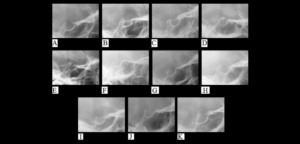

La anquilosis temporomandibular es una enfermedad que afecta a la ATM. Suele causar limitación de la apertura bucal y deformidad facial, especialmente en pacientes jóvenes.